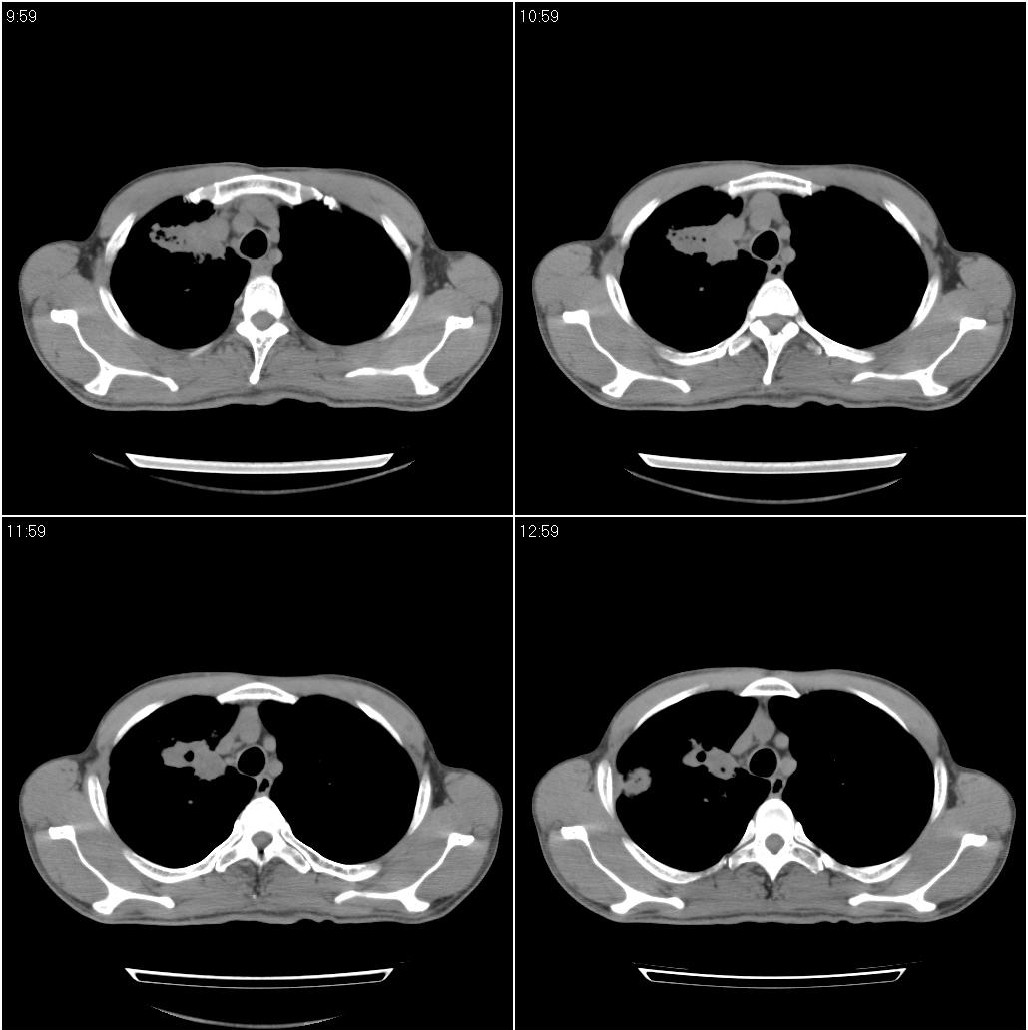

双肺继发性肺结核

肺脓肿!

两肺继发性肺结核并多发性结核球形成,部分病灶内空洞形成。

符合继发性结核表现部分空洞形成并播散